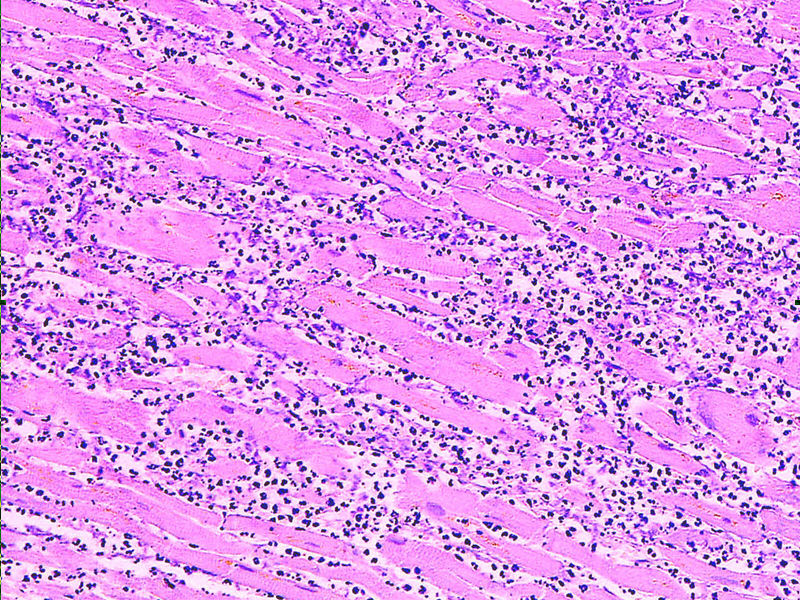

back myocardial infarct

Source: Myocardial infarct emmolition phase histopathology.jpg